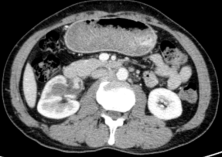

广泛开展腹腔镜下肾癌根治术、肾盂癌根治术、肾部分切除术、肾肿瘤剜除术、肾上腺肿瘤切除术、肾盂输尿管成形术、肾囊肿去顶减压术、输尿管上段切开取石术等。全腔镜下进行,创伤小、恢复快。

腹腔镜肾肿瘤剜除术(保肾) 腹腔镜肾癌根治术 腹腔镜肾盂癌根治术